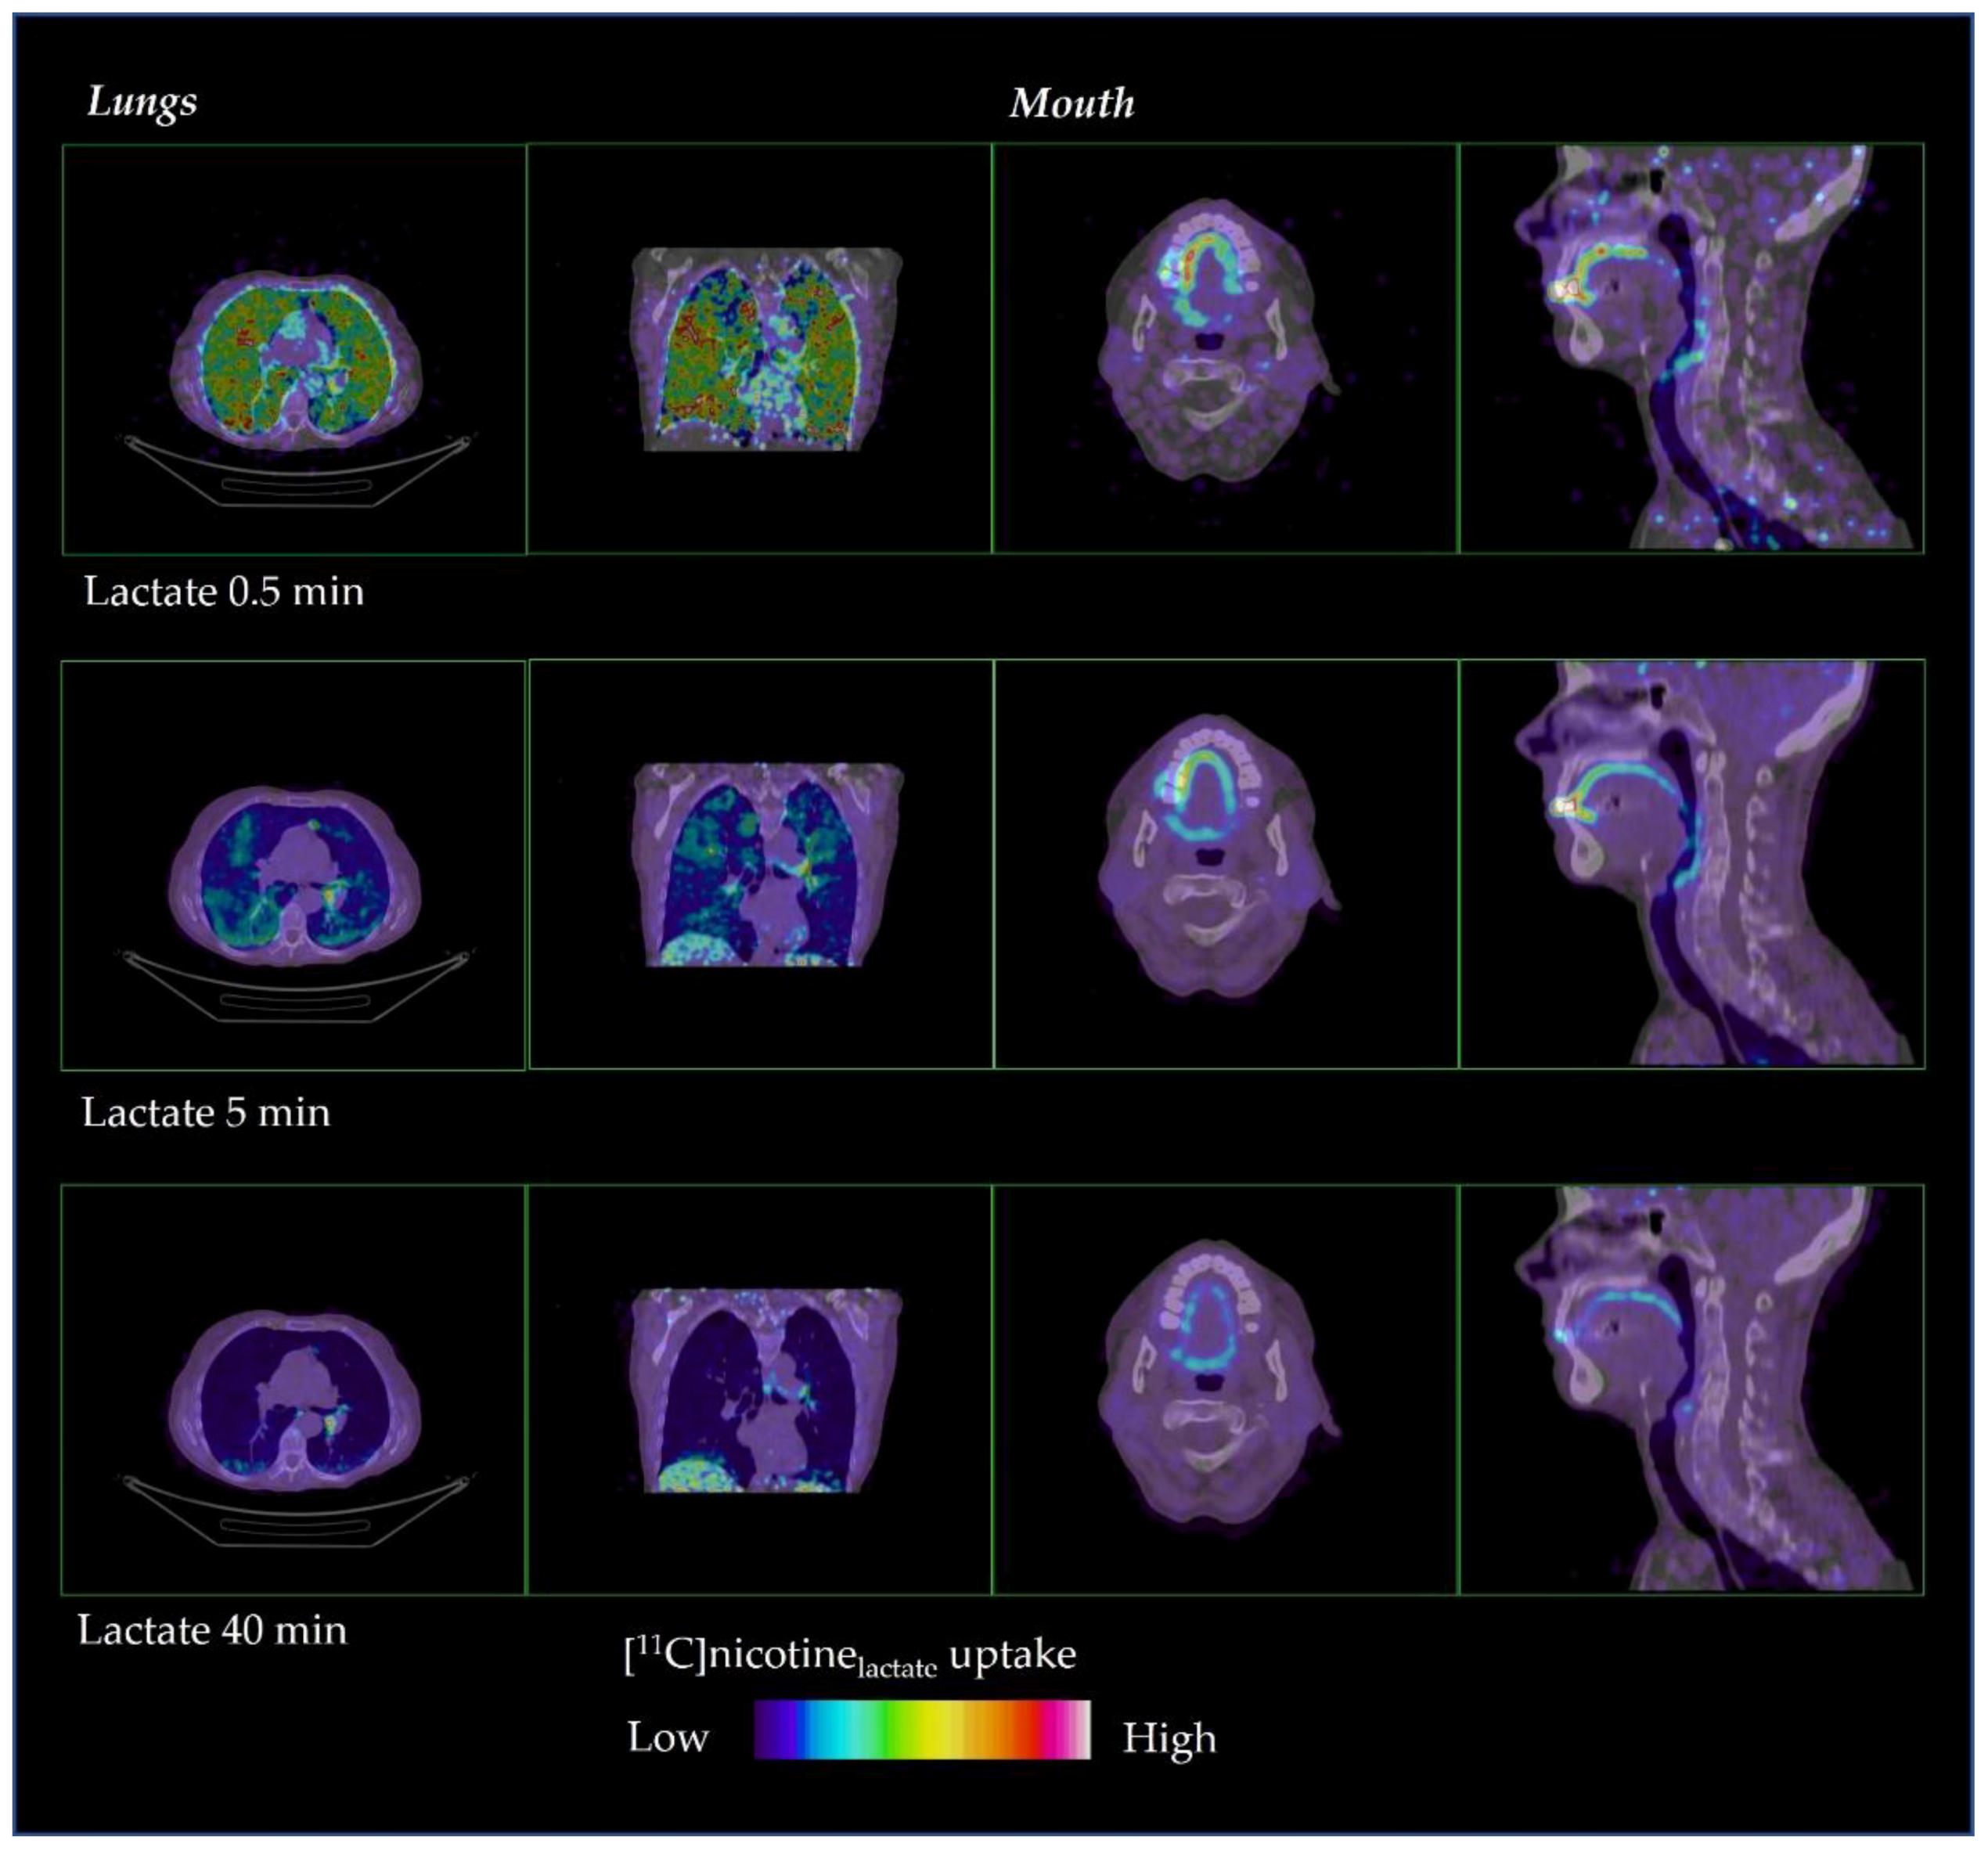

The distribution of [11C]nicotine over time is shown in Figure 2 and Figure 3 for freebase nicotine and nicotine lactate formulations, respectively. The same subjects are considered as in Figure 1.

Figure 3.

Representative distribution of [11C]nicotinelactate in lungs and mouth at 0.5, 5 and 40 min after inhalation.

A fast distribution was also observed for [11C]nicotinelactate with a rapid passage through the oral cavity, upper respiratory pathways and the bronchial tree (Figure 3). However, the [11C]nicotine from the lactate formulation accumulated less in those regions compared to the freebase formulation. [11C]nicotinelactate reached the entire lungs beyond the bronchial tree faster and to a greater extent than [11C]nicotinefreebase.